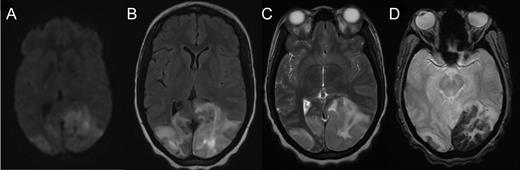

Cranial computed tomography (CT) demonstrated subtle hypodensity mainly in the left occipital lobe, with a characteristic empty delta sign (Fig. 1). Computed tomography angiography demonstrated normal filling of the posterior cerebral arteries (PCA). Cranial magnetic resonance imaging (MRI) evaluations demonstrated bilateral ischemic changes involving the occipital and parietal lobes, more extensively on the left (Fig. 2). Magnetic resonance venography (MRV) demonstrated complete occlusion of the left transverse and sigmoid sinuses, as well as near occlusion of the posterior superior sagittal sinus (Fig. 3C).

Axial MRI demonstrating cerebral tissue injuries from venous hypertension with the associated ischemia: (A) Diffusion-weighted imaging (DWI) MRI. (B) Fluid-attenuated inversion recovery (FLAIR) imaging. (C) T2-weighted MRI. (D) Gradient-echo (GRE) imaging.

In our patient, the combined occlusion of the posterior third of the superior sagittal sinus and the left transverse sinus likely resulted in severe venous hypertension affecting the bilateral visual cortices with subsequent incomplete infarction. Incomplete bilateral infarction of the visual cortices can present with a remarkable variety of syndromes, with some cases having begun as complete blindness. Although patients with complete cortical blindness commonly volunteer no complaints and are unaware of the deficit [5], our patient acutely presented with the primary complaint of bilateral visual loss.